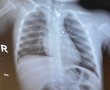

לראשונה בישראל: השתלת לב מלאכותי שהחליף לחלוטין את ליבו של החולה

חייו של מטופל בן 63 ניצל הודות להשתלת לב מלאכותי שלם שבוצעה השבוע לראשונה בארץ - בהדסה עין כרם, במבצע שהוביל צוות רפואי נרחב שכלל קרדיולוגים, כירורגי לב, מומחים בהרדמה וטיפול נמרץ, אחי חדר ניתוח וטכנאי מכונת לב ריאה.